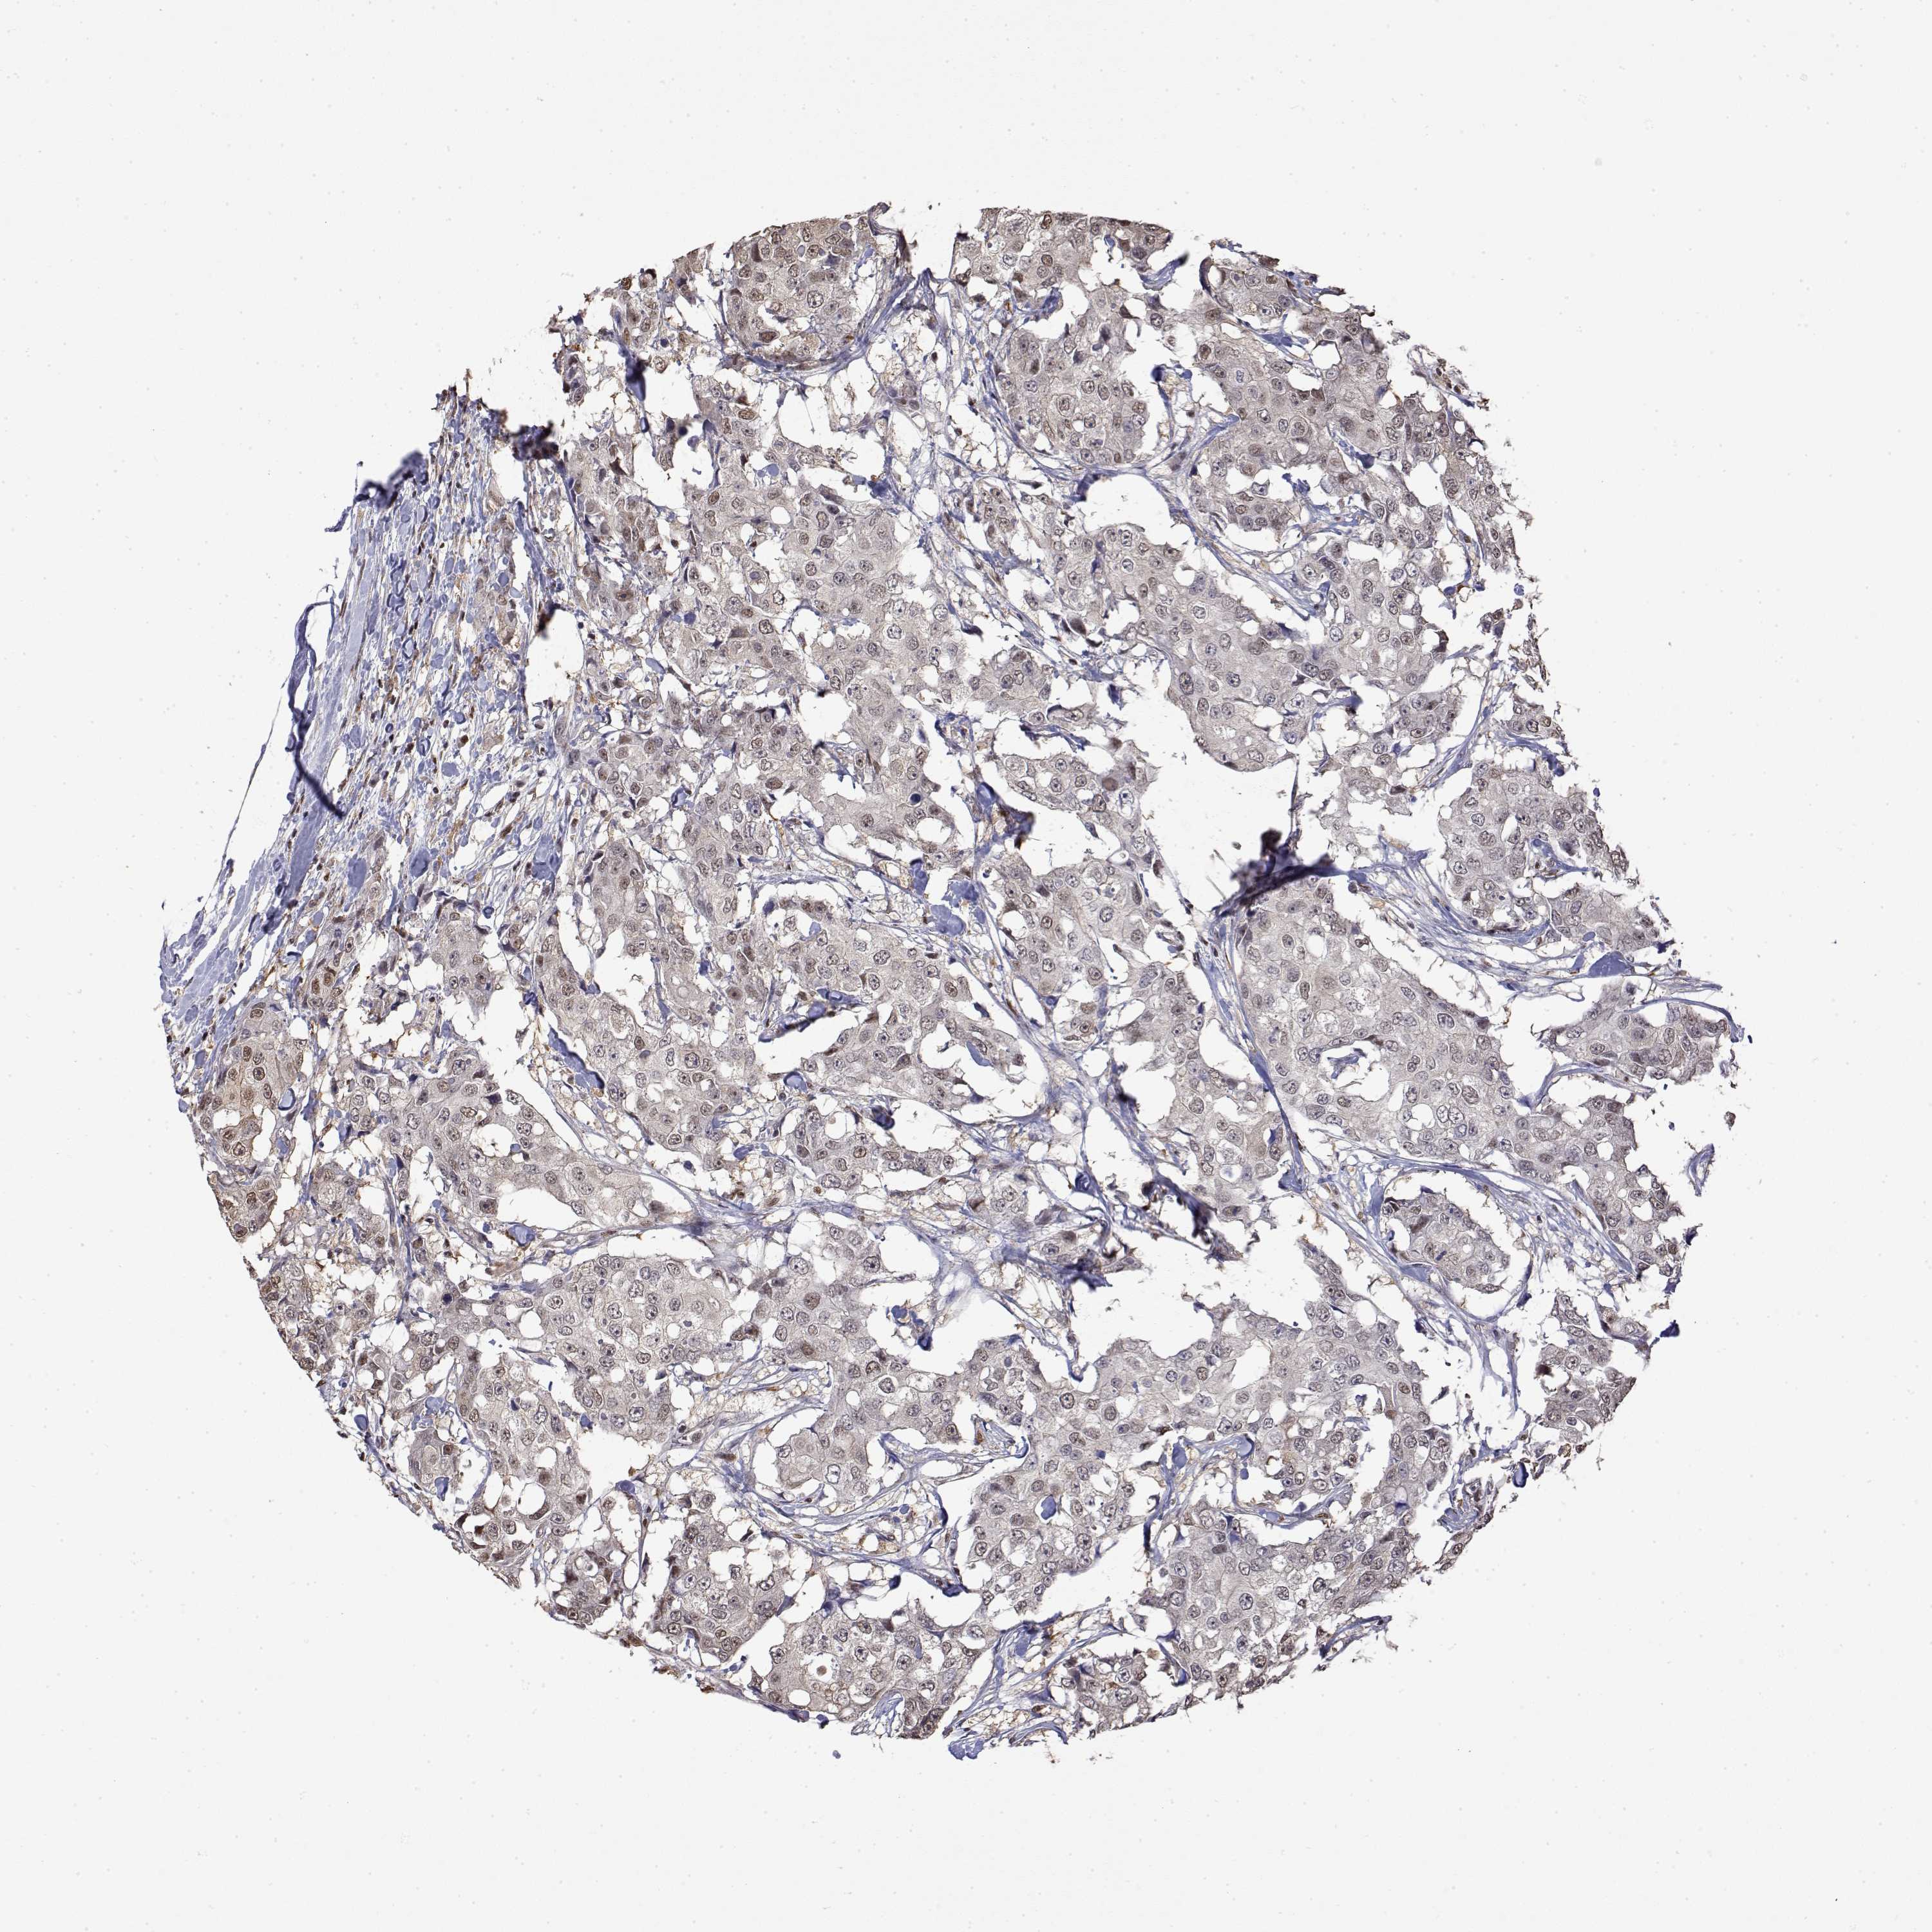

BRCA TCGA BRCA VALIDATION PROTEIN EXPRESSION